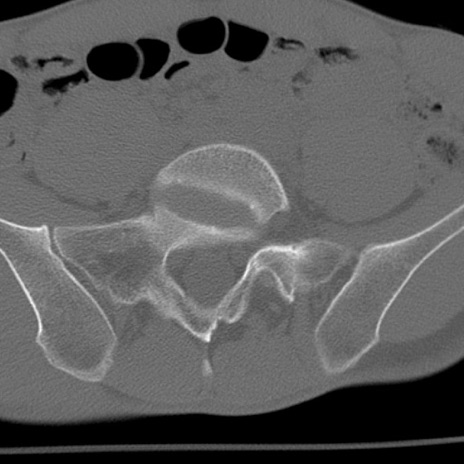

症例3 腰椎CT(横断像)

腰椎CT